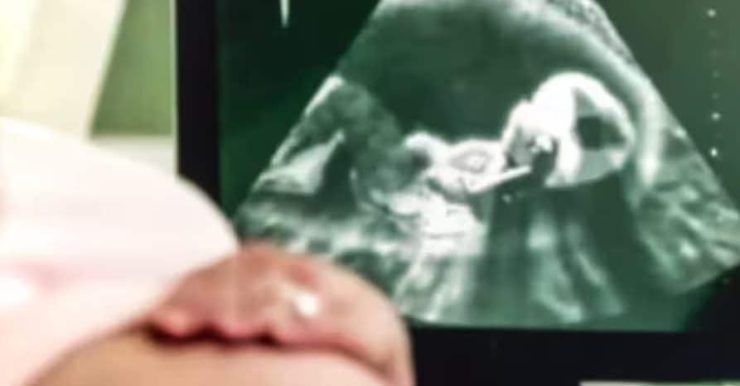

Durante tutta la gravidanza, rassicurazioni a non finire: “Va tutto bene, signora. Nessun problema, il bimbo cresce bene.” Lei si è fidata, come farebbe chiunque. Ma la notte di Natale 2015, all’ospedale Maggiore, la realtà è piombata addosso a tutti: Bryan nasce senza gambe dal ginocchio in giù. Una botta che ha stravolto la famiglia, e che solo adesso – dieci anni dopo – trova risposta in tribunale.

Il tribunale, con la giudice Cristina Ferrari, ha accolto le tesi degli avvocati della famiglia, Silvia Gamberoni e Alessandro Falzoni. Hanno messo in fila prove inconfutabili: la mamma s’è fatta un’infinità di ecografie, sia dal ginecologo privato che in consultorio, e nessuno si è accorto della malformazione. Nessuno. Neanche per sbaglio.

La sentenza è lapidaria: “È pacifico che nessun medico abbia rilevato prima della nascita la malformazione, nonostante i molteplici esami.” Tradotto: una negligenza enorme, senza scuse possibili. Le perizie hanno pure confermato che quasi tutte le ecografie sono state lette male. Un errore così grosso non succede per caso, ma per superficialità e poca attenzione.